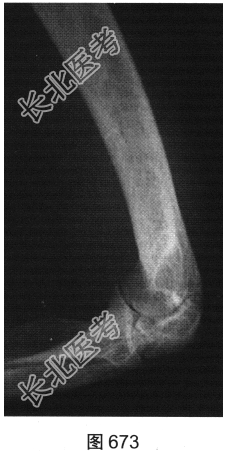

- [材料题] 患者女性,62岁,右侧肘关节肿胀、疼痛1年余。肘关节正侧位X线片及CT检查见图673~图676。

- 简答题1、请对该患者影像征象进行描述。

- 简答题2、根据题干中患者的临床表现及影像特征,请问该患者应首先考虑哪种疾病?